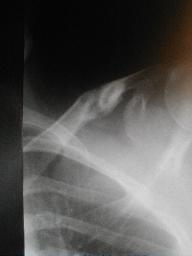

| 1月15日午前 |

1月15日午後 |

1月22日

末梢骨片の捻転変位が気になる

骨折端に綿花をあて圧迫を強くする |